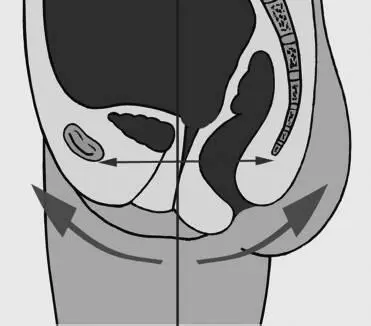

Правильно стоящий таз является основой, фундаментом всех сегментов тела, которые находятся выше – живот, грудь, шея, голова. Его корректное положение становится одним из основных базовых моментов, обеспечивающих правильную осанку и энергетическое здоровье тела. В норме при правильном положении таза лонная кость (лобок) и кость крестца должны быть направлены друг на друга, образно говоря, как вогнутое и выгнутое зеркала (рис. 74).

Рис. 74. Нормальное положение таза